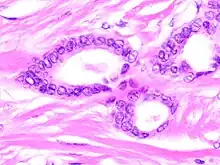

Tubular carcinomas are generally around 1 cm. or smaller, and are made up of tubules. They are usually low-grade.[2] Elastosis has been noted as common but is not present in all cases.[11]

- Image by Mikael Häggström, MD. Reference for typical features: Pragya Virendrakumar Jain, M.D., Julie M. Jorns, M.D. "Breast - Other invasive carcinoma subtypes, WHO classified - Tubular". Pathology Outlines.

A highly differentiated invasive carcinoma that forms well-defined tubules (containing epithelium, but no myoepithelium) and that have abundant desmoplastic fibrous stromal reaction between the tubules.